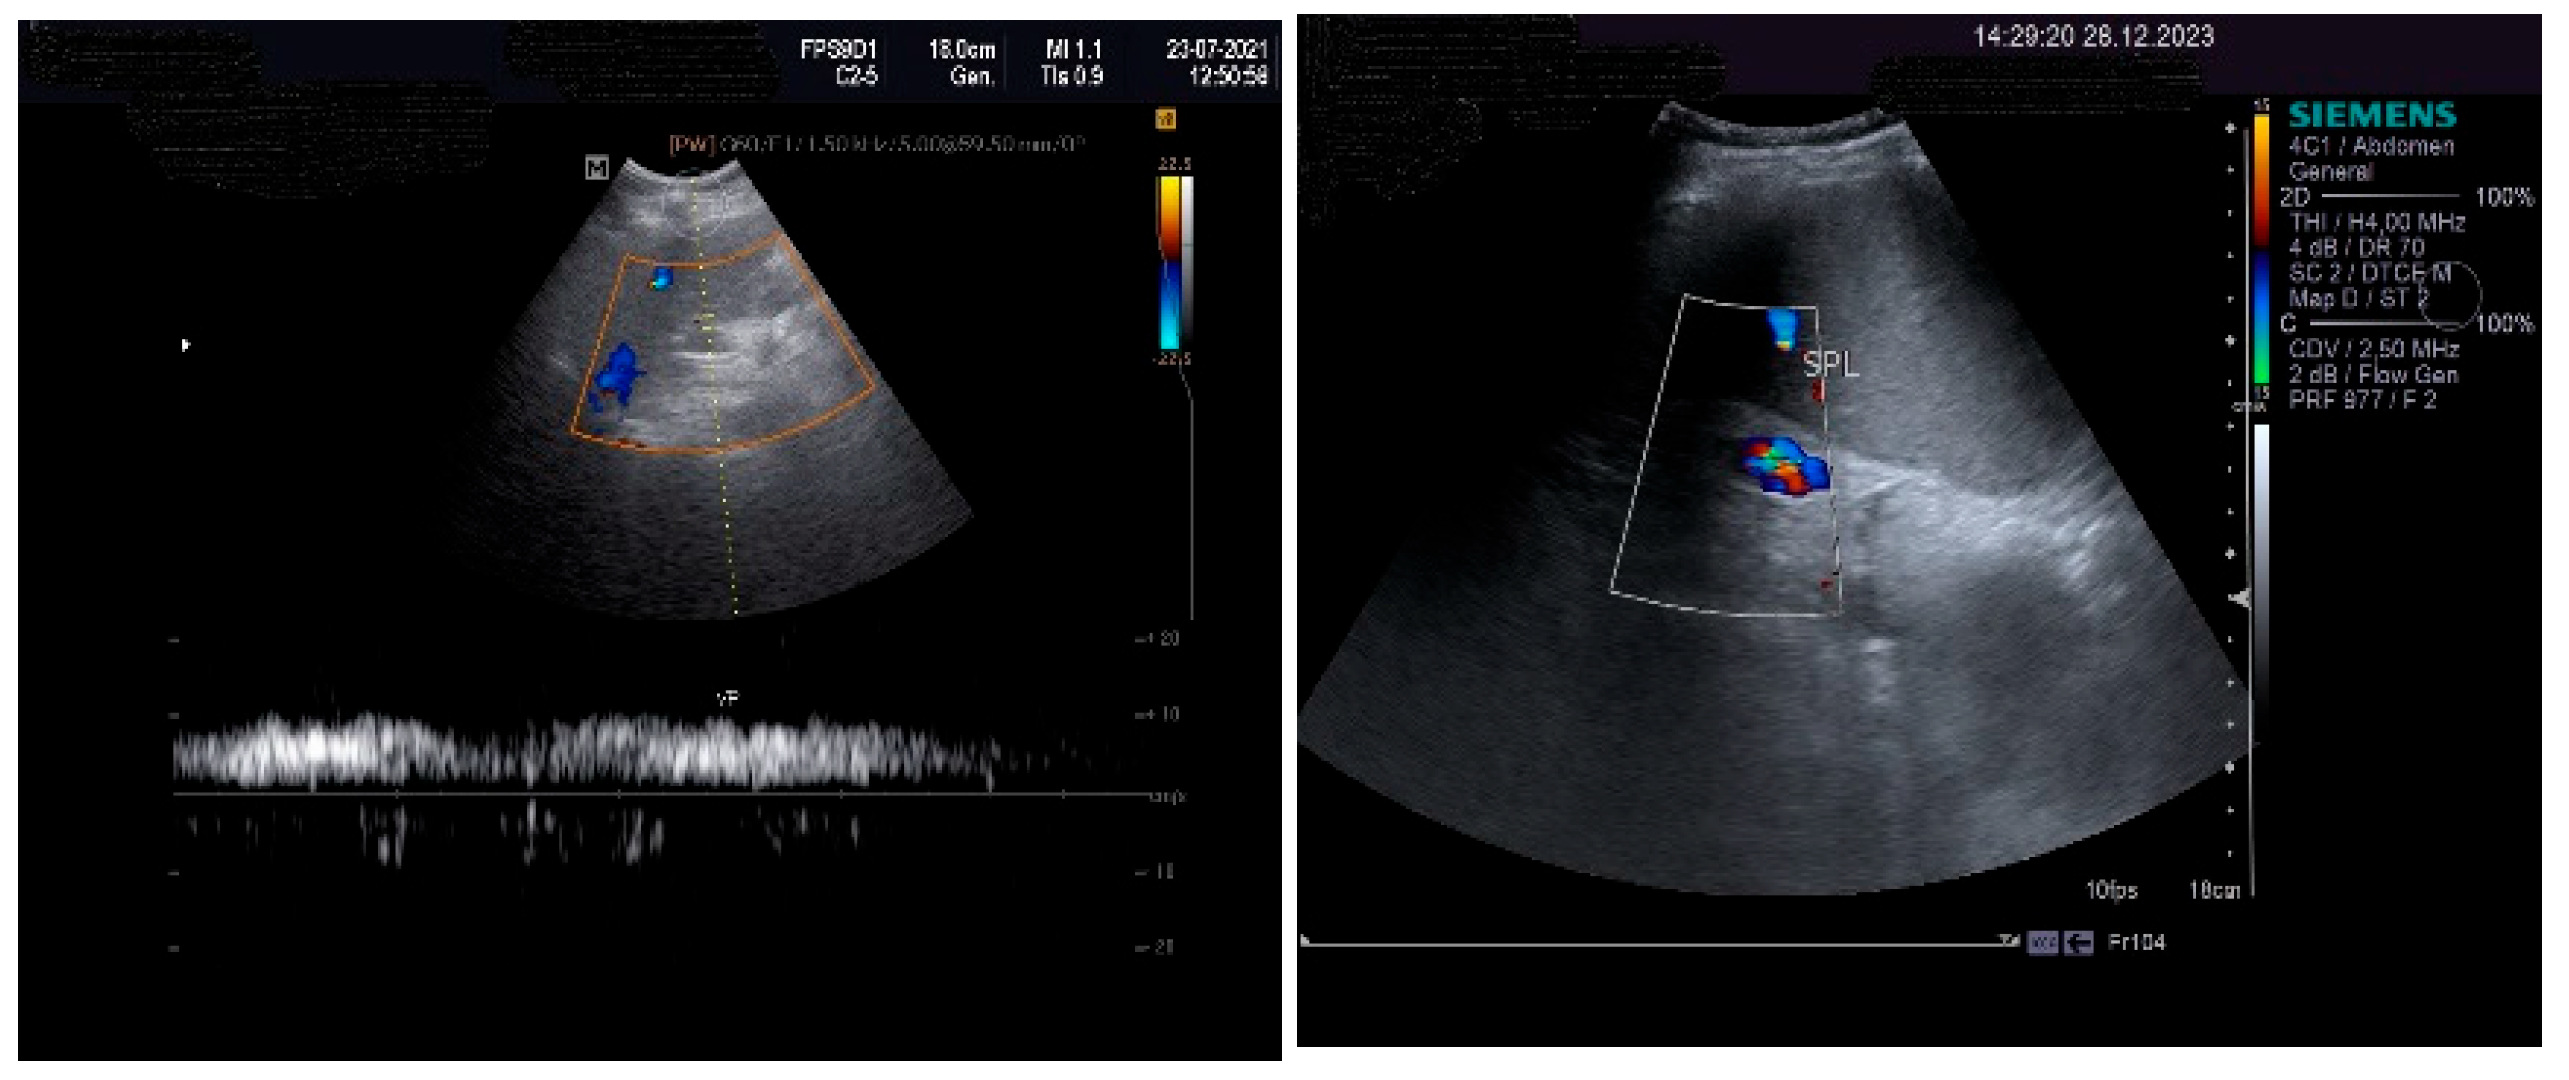

The pulsed Doppler ultrasound revealed a patency of the main portal vein as well as of the left and right portal branches and decreased, demodulated hepatopetal portal venous flow, with mildly decreased respiratory variability in the amplitude of the portal vein flow. The Dopler aspects of the liver and spleen are illustrated in Figure 4.

The measurements of the resistivity index of the hepatic artery at the liver hilum revealed increased values (HARI = 0.79). However, the liver elastography demonstrated a low stiffness. The measurements were made using the acoustic radiation force impulse (ARF)I method, by point shear wave (p SWE) elastography, and the obtained median value was 1.24 m/s, IQR = 0.12, equivalent to an F2 Metavir fibrosis score. Therefore, the diagnosis of liver cirrhosis was highly improbable. The elastography of the right liver lobe performed by the ARFI method, pSWE, is presented in Figure 5.

An important role in the imaging diagnostic approach of SOS/VOD is played by ultrasonography. According to some studies, it seems that ascites and gallbladder wall edema represent independent predictors in SOS/VOD diagnosis. Some authors reported that the thickness of the gallbladder wall correlated well with the HVPG. This particular aspect of the markedly thickened GB wall was also observed in the presented patient, associated with ascites and increase in the HVPG. Pulsed Doppler ultrasound is also useful for suggesting SOS/VOD, based on the study of the venous portal flow, which can be decreased or reversed. A significant increase in the HARI may also be associated with liver injury. Hepatic and portal flow anomalies revealed by duplex examination seem to correlate with the HVPG. However, as we have also noted, the reversed portal venous flow is not always recorded and, therefore, one cannot exclude SOS/VOD based on the absence of the hepatofugal portal flow sign [28]. The patient that we have presented in this case report displayed no reversed portal venous flow, but increased values of the HARI.

Figure 4. Doppler examination. Liver: pulsed Doppler of the portal vein (left). Spleen: color Doppler of splenic vein (right).